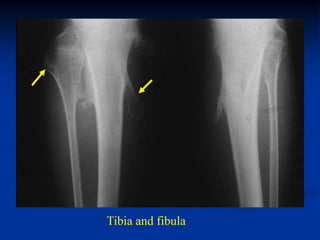

CLASSIC        Case #625

15 year male with multiple hereditary exostoses

Tibia and fibula

Lateral view